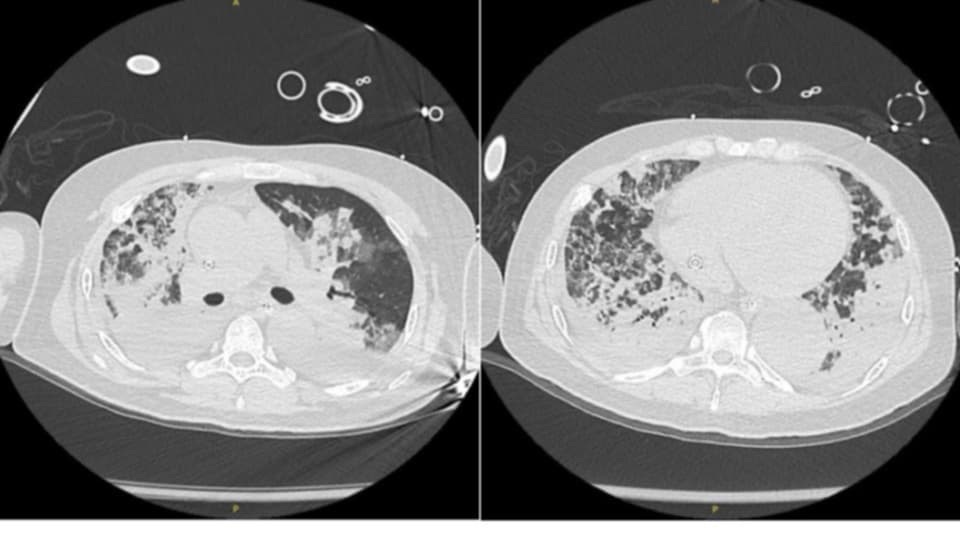

這次準備MM時選擇了我自己在過年期間CCU遇到的病人,一名近30歲年輕男性,無已知underlying diseases,一開始是因為喘以及呼吸道症況約兩週,逐漸惡化越來越喘以後先去外院。在外院急診因為太喘以及氧氣不穩定,就直接被插管了。外院CXR看起來bilateral diffused GGOs and consolidation,心臟超音波看起來LVEF約只有20%-30%合併global hypokinesia ,被轉來我們的急診。在急診因為O2太差,心臟也動得不好,所以就直接放了V-A-V ECMO 給予病人支持。

雖然我們做了一些survey,患者並無明顯的 CAD or heart failure risk factdors,但是因為心臟超音波看起來動得不好,EKG也有一些懷疑缺血的證據,結果coronary angiography 真的發現在RCA distal segment 有塞住,最後放了支架打通血管。肺部的部分,雖然使用廣效性抗生素以及利尿劑脫水後,患者的CXR有明顯進步,但卻沒有找到明顯的 infection focus。後來 V-A-V ECMO 成功 weaning 掉,患者也平安順利地出院回家,卻還是有很多問題沒有找到明顯的解釋(高血壓、單邊腎臟萎縮)。